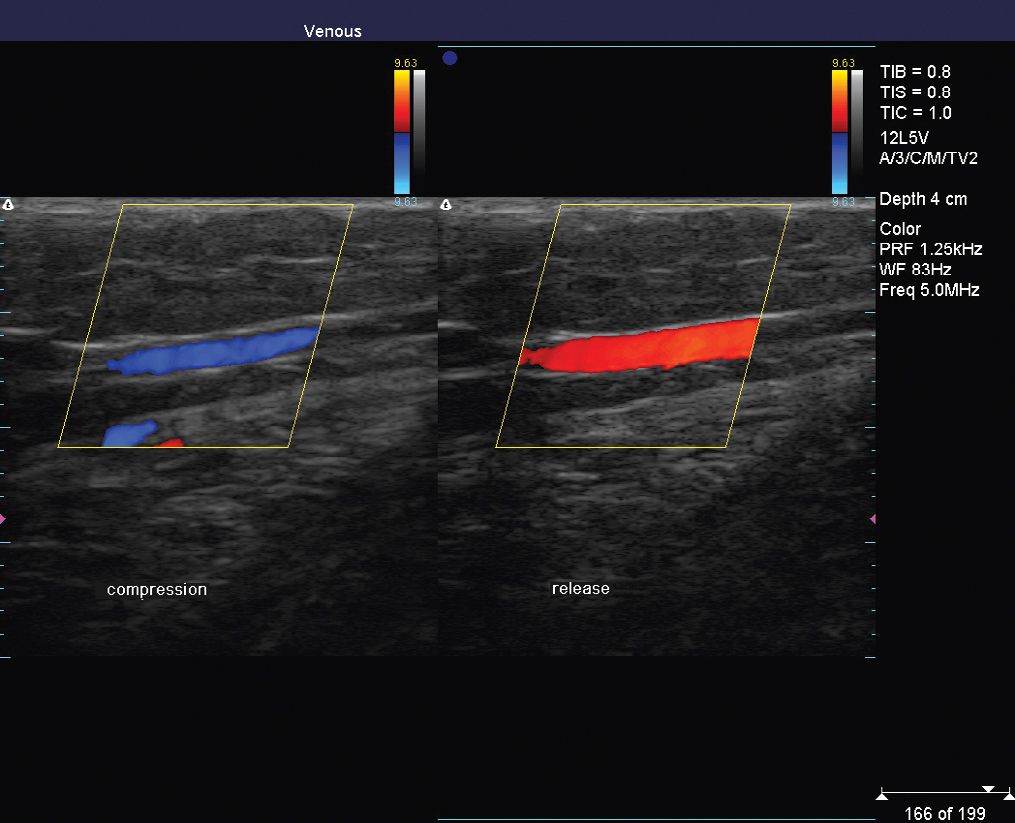

Venous Imaging/Duplex Ultrasound Plastic Surgery Key What Does A Venous Duplex Show The name “duplex ultrasound” refers to the fact that this type of test incorporates two. Duplex ultrasound involves using high frequency sound waves to look at the speed of blood flow, and structure of the leg veins. Venous ultrasound uses sound waves to produce images of the veins in the body. Explain how to perform a complete duplex. Arterial and. What Does A Venous Duplex Show.